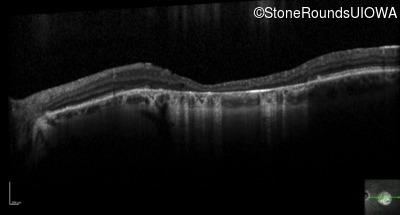

Optical Coherence Tomography - Right - 20/63 -2

Exemplar / OCT Stack